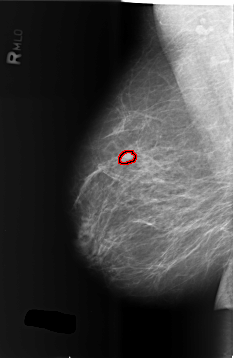

B_3432_1.RIGHT_MLO

RIGHT_MLO LINES 5720 PIXELS_PER_LINE 3736 BITS_PER_PIXEL 12 RESOLUTION 50 OVERLAY

FILE: B_3432_1.RIGHT_MLO.OVERLAY

TOTAL_ABNORMALITIES 1

ABNORMALITY 1

LESION_TYPE MASS SHAPE LOBULATED MARGINS CIRCUMSCRIBED-OBSCURED

ASSESSMENT 4

SUBTLETY 4

PATHOLOGY BENIGN

TOTAL_OUTLINES 1

BOUNDARY